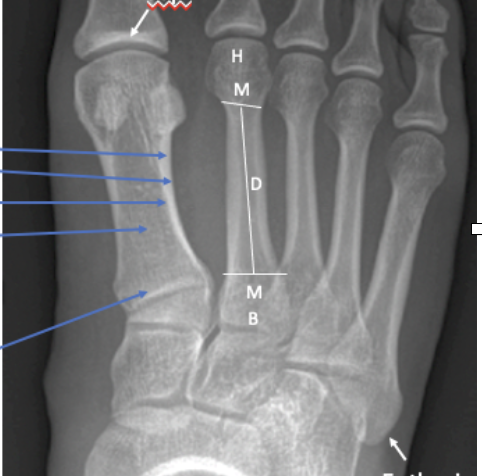

Q

What view is this?

A

Medial Oblique